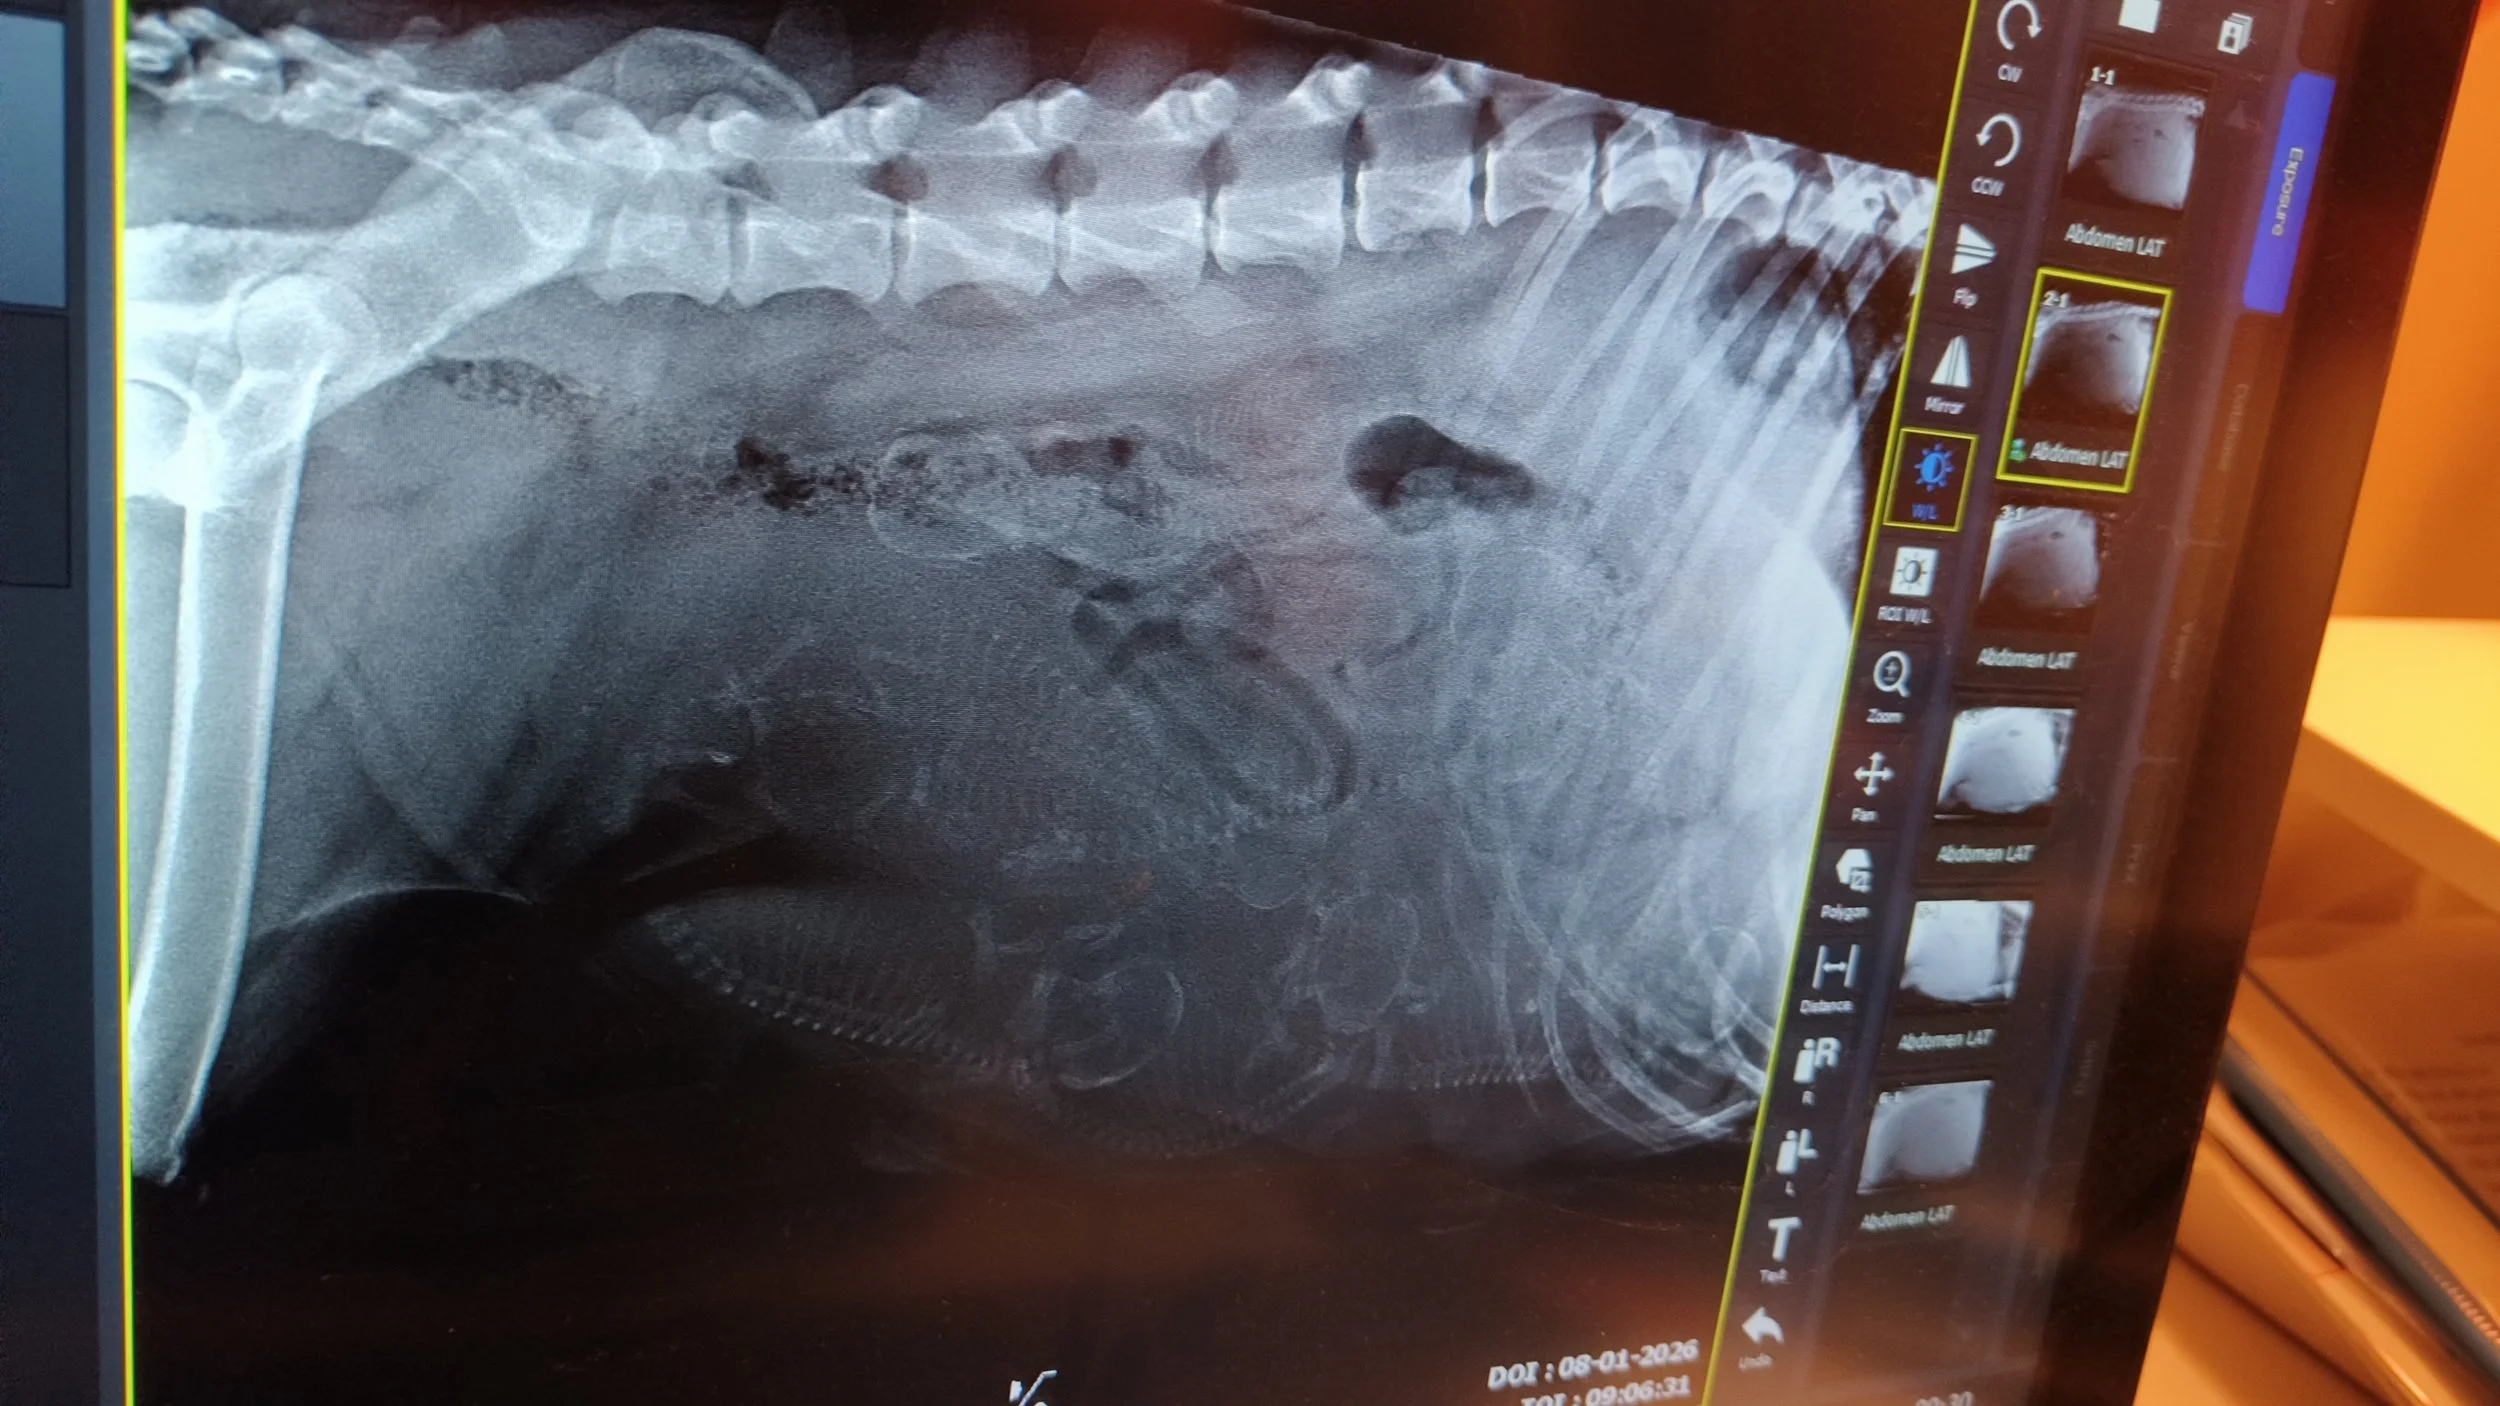

8. januar viste røntgen, at Juno ventede 7 hvalpe. Fødekassen var klar, og nu var det bare at vente på, at Juno også blev klar. 15. januar gik fødslen i gang, men da der pludselig kom grønt fostervand, måtte Juno af sted til dyrlægen, og det endte med kejsersnit. 2 hvalpe var døde 1 - 2 dage før fødslen, men Juno kom hjem med 5 dejlige hvalpe, 4 piger og en meget lille dreng. Selvom han fik tilskud lige fra starten og han suttede fint, tog han ikke på, og 6 dage efter fødslen måtte vi i samråd med dyrlægen lade vores lille Cliff sove ind - dyrlægen mener ikke, hans fordøjelsessystem var færdigudviklet. Det var hårdt, men nu ligger han begravet i haven sammen med de andre døde familiedyr. Og vi glæder os helt enormt over Cove, Caye, Cape og Crest. De trives og vokser synligt fra dag til dag. Juno er en meget dygtig hundemor og passer dem til UG.